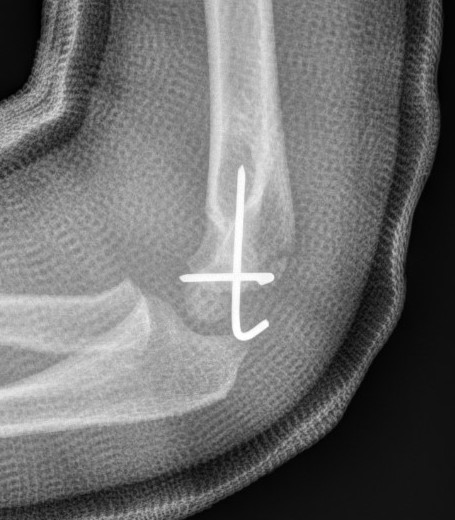

X-ray

Undisplaced

- typically metaphyseal flake

- looks minimally displaced on AP and lateral

- perform an internal oblique x-ray to exclude displacement